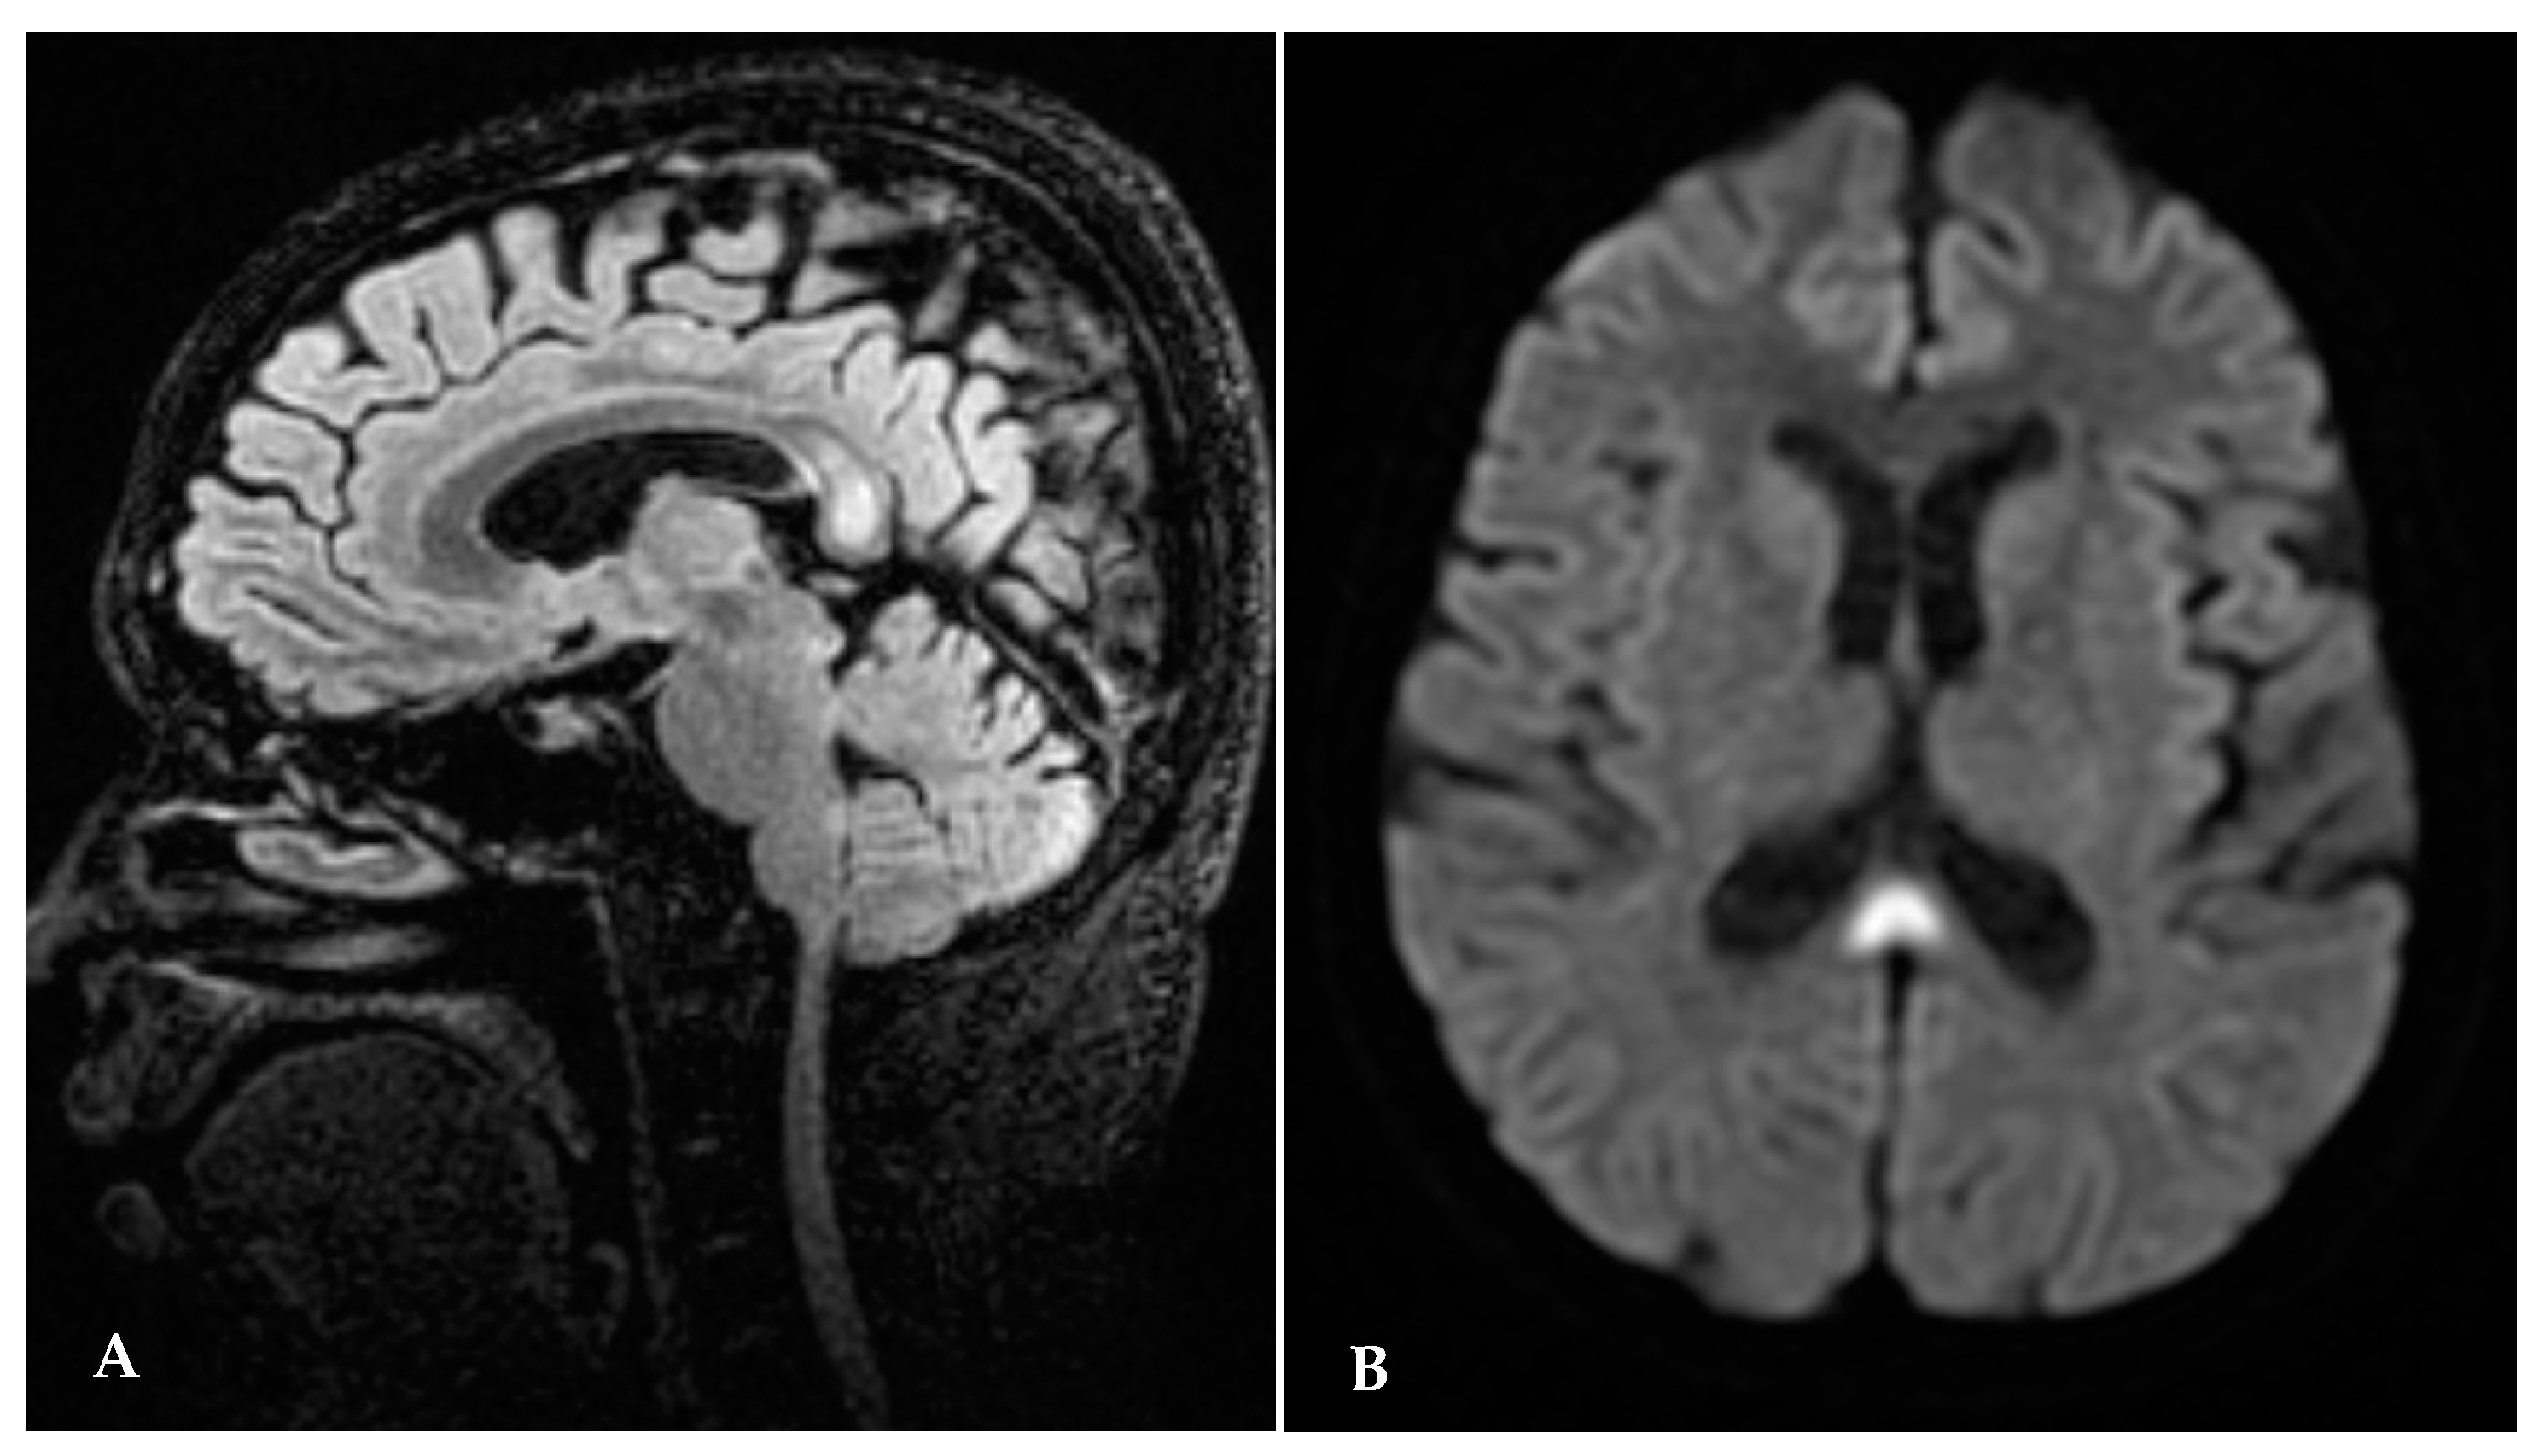

A second brain MRI, performed seven months after the beginning of thiamine replacement and one month after delivery, showed hyperintensity to have completely disappeared in the splenium of corpus callosum in thalamic and periaqueductal areas (Figure 2A,B).

Figure 2.

(A,B) Brain MRI seven months after thiamine start: disappearance of abnormal signal.